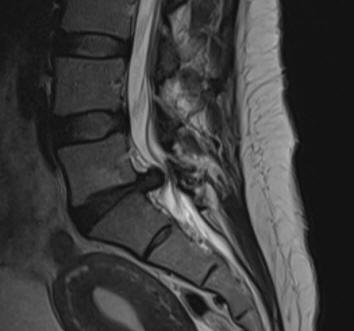

29-DECEMBER-2019  MASHAEL ISMAEEL MUHAMED  46 YEARS  HUGE EXTRUDED DISC L5-S1 WITH LEFT FORAMINAL OCCLUSION.

The patient came to the clinic 28-December-2019 with severe LBP and agonizing left sciatica, pain and numbness left S1 territory for 2 months. MRI lumbar spine performed 23-December-2019 showing huge extruded disc L5-S1 with left foraminal occlusion.

Fig-1: The extruded disc L5-S1.